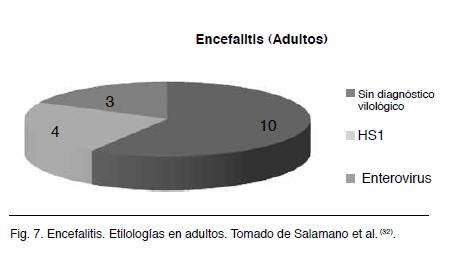

En este trabajo se detectaron 44 pacientes con clínica y paraclínica sugestivas de encefalitis viral; 21 de estos casos no tuvieron diagnóstico etiológico viral por PCR; 27 casos fueron encefalitis en niños mayores a seis meses y 17 en adultos; 17 tuvieron diagnóstico virológico vinculado a virus de la familia herpes: 11 por HSV 1, 3 por CMV, 2 por VZ y 1 por HSV 2. Es de destacar que los hallazgos de CMV, VZ y HSV 2 fueron en niños. Ninguno de los pacientes tenía circunstancias de inmunodepresión (Figuras 6 y 7).